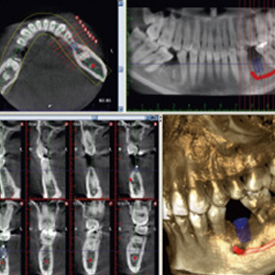

インプラントシミュレーションシステム - SIMPLANT -

インプラント治療を行う前には、CTで撮影した画像やデータを元に、コンピューター上でインプラント治療専用ソフトを用いたシミュレーションを行います。

3D解析による精密なシミュレーションを行うことで、血管や神経を傷付けることなく、より安全・安心にインプラント治療を行うことができます。